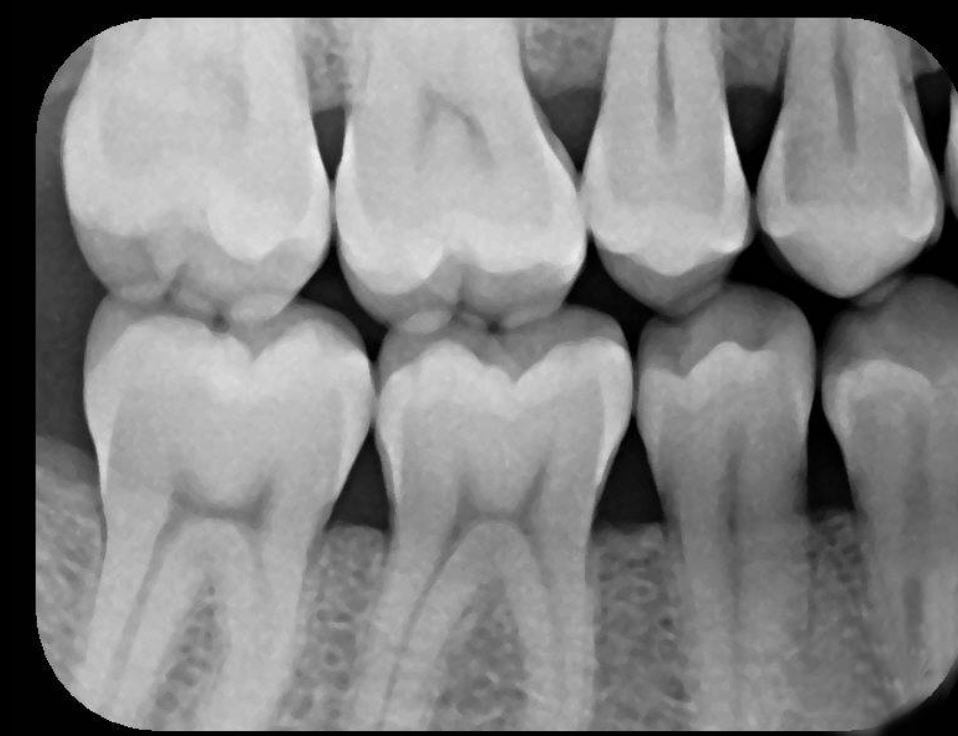

X-Ray 2: How many caries are present?

(Required)

X-Ray 2: How many PAP's are present?

X-Ray 3: How many caries are present?

X-Ray 3: How many PAP's are present?